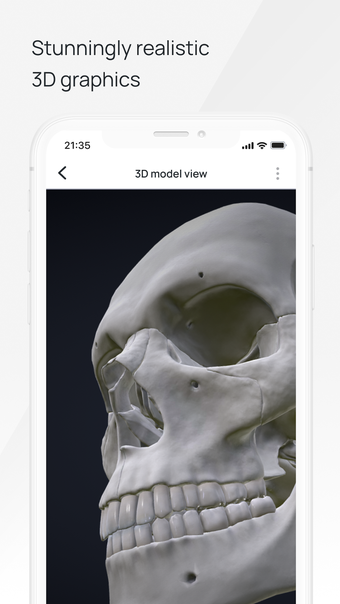

In this atlas of human pathologies you can learn about diseases, their causes, symptoms, and treatment. It contains all the essential information about the anatomy of the human body and its organs. You will be able to study diseases and their causes from an anatomy point of view. It contains information about diseases, their symptoms, and their treatment. In addition, you will be able to view 3D models of all the important organs of the human body.

All 3D pathology models are developed in close cooperation with medical experts of hospitals and research centers. They are thought out to the very smallest detail. Each category contains models of healthy organs.